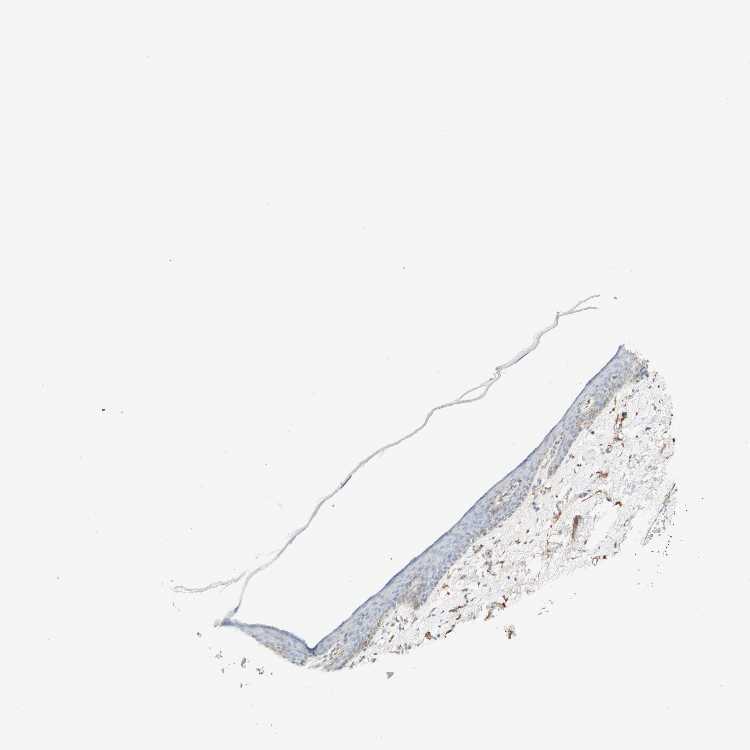

SKIN 1 - Antibody stainingi

Antibody staining in the annotated cell types in the current human tissue is reported as not detected, low, medium, or high, based on conventional immunohistochemistry profiling in selected tissues. This score is based on the combination of the staining intensity and fraction of stained cells.

Each image is clickable and will lead to virtual microscopy that enables deeper exploration of all samples and also displays staining intensity scores, fraction scores and subcellular localization as well as patient and tissue information for each sample.

Antibody HPA012122Antibody HPA015130

Langerhans Not detectedNot detected

Fibroblasts MediumNot detected

Keratinocytes Not detectedNot detected

Melanocytes Not detectedNot detected